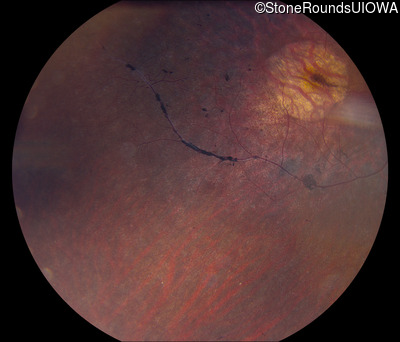

Fundus Photography - Right - 20/50

Exemplar